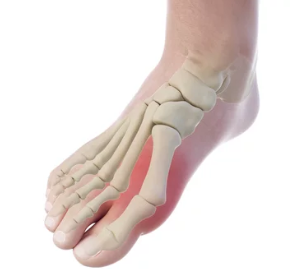

무지외반증(Hallux Valgus)은 엄지발가락이 안쪽으로 휘어지며 발톱이 바깥쪽으로 돌출되는 질환입니다. 이로 인해 발에 불편함을 느끼거나 심한 통증을 유발할 수 있으며, 걷거나 서 있는 동안 큰 어려움을 겪기도 합니다. 특히 여성에서 더 많이 발생하는 이 질환은, 발의 구조적 변형으로 인해 일상생활에 지장을 줄 수 있습니다. 무지외반증을 조기에 발견하고 적절한 치료를 받는 것이 중요합니다. 이번 글에서는 무지외반증의 원인, 증상, 치료 방법, 예방 방법까지 모든 정보를 상세히 다뤄보겠습니다.

(1) 엄지발가락 휨

무지외반증의 가장 흔한 증상은 엄지발가락이 안쪽으로 휘어지는 현상입니다. 엄지발가락이 점차 안쪽으로 휘어져 발톱이 바깥쪽으로 돌출되며, 발가락의 변형이 진행됩니다.